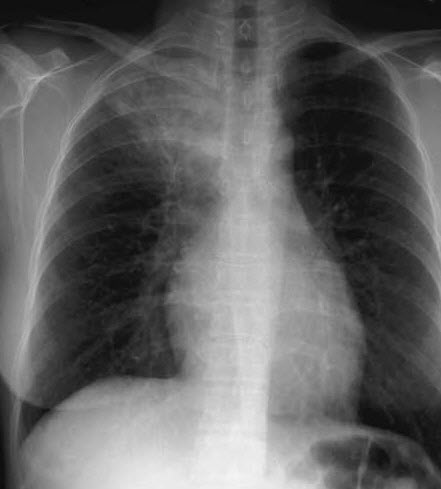

The patient was seen at a local urgent care center and treated with levofloxacin for a week. A chest radiograph showed infiltrates in the right upper lobe. The symptoms worsened and the medication was switched to clarithromycin, but there was no marked improvement.

A chest radiograph and sputum evaluation for acid-fast bacteria (AFB) are ordered.

A high index of suspicion is warranted. The diagnosis is confirmed by demonstration of AFB either in biopsy material or sputum, in conjunction with sputum culture. Chest radiography or CT can be helpful.